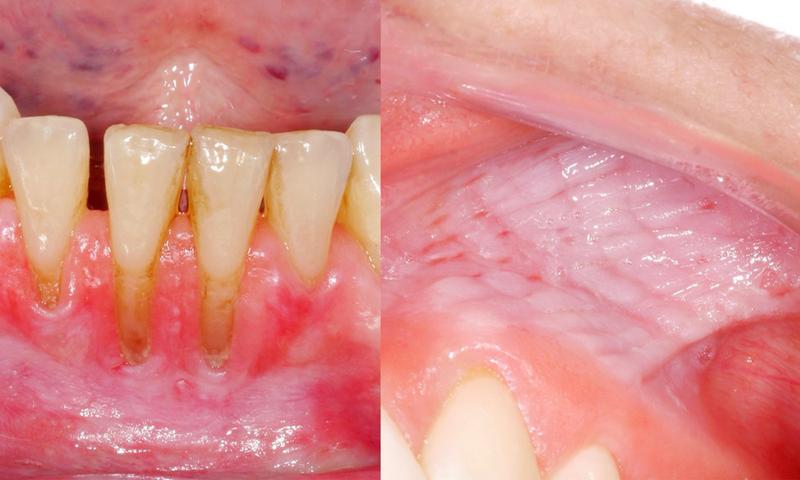

Możliwe, że zastanawiasz się, czy snus jest bezpieczniejszy niż papierosy. Chociaż w przypadku snusów nie wdychasz dymu, nie oznacza to, że są one wolne od zagrożeń. Użytkownicy często zauważają zwiększone ciśnienie krwi oraz ryzyko chorób sercowo-naczyniowych, które mogą prowadzić do zawałów serca czy udarów. Ponadto, na dłuższą metę snus przyczynia się do uszkodzenia jamy ustnej, co skutkuje stanami zapalnymi dziąseł i innymi problemami stomatologicznymi. Od czarnych plam na zębach po nowotwory – niestety, snus nie jest przyjacielem w sąsiedztwie!

- Problemy stomatologiczne – stan zapalny dziąseł i inne problemy zdrowotne w jamie ustnej.